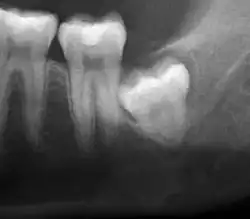

El diagnóstico de impactación se puede hacer clínicamente si es visible una parte suficiente de la muela del juicio para determinar su angulación y profundidad, y si el paciente es lo suficientemente mayor como para que sea improbable una erupción o enderezamiento posterior. Las muelas del juicio continúan moviéndose hasta la edad de 25 años debido a la erupción, y luego continúan algún movimiento posterior debido a la enfermedad periodontal.[18]

Si el diente no se puede evaluar únicamente con el examen clínico, el diagnóstico se realiza mediante una radiografía panorámica o una tomografía computarizada de haz cónico. Cuando las muelas del juicio no erupcionadas todavía tienen potencial de erupción, se utilizan varios factores predictivos para determinar la probabilidad de que los dientes se impacten. La relación de espacio entre la longitud de la corona del diente y la cantidad de espacio disponible, el ángulo de los dientes en comparación con los otros dientes son los dos predictores más utilizados, siendo la relación de espacio la más precisa. A pesar de la capacidad de movimiento en la edad adulta temprana, la probabilidad de que el diente se impacte puede predecirse cuando la relación entre el espacio disponible y la longitud de la corona del diente es inferior a 1.:[5] 141